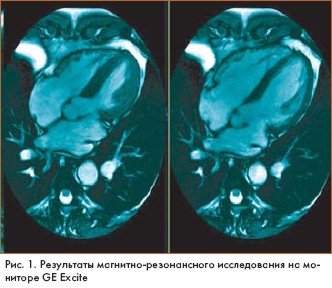

Магнитно-резонансные изображения (magnetic resonance imaging - MRI), полученные на основе высокоскоростного сканирования с помощью технологии GE Excite, открывают новые возможности хорошо известного метода исследования. Идея была представлена на 10-й научной конференции Международного общества Magnetic Resonance in Medicine, которая прошла в США.

Система GE Excite была разработана компанией GE Medical Systems (США). Высокая скорость сканирования и компьютерной обработки данных позволяет получать объемные MR-изображения высокого разрешения в реальном времени, например в процессе работы сердца.

"Мы впервые получили возможность получать изображения в процессе реальной жизнедеятельности органов, - говорит доктор Lawrence Tanenbaum из Института неврологии Нью Джерси (США). - GE Excite не требует задержки дыхания в процессе исследования больных и особенно удобна для получения качественных изображений органов, находящихся в движении, например сердца и сосудистой системы"

Представители GE Medical Systems заявляют, что новая технология позволит врачам улучшить качество и информативность диагностики заболеваний сердца, последствий инсульта, желудочно-кишечной патологии, ортопедических нарушений.